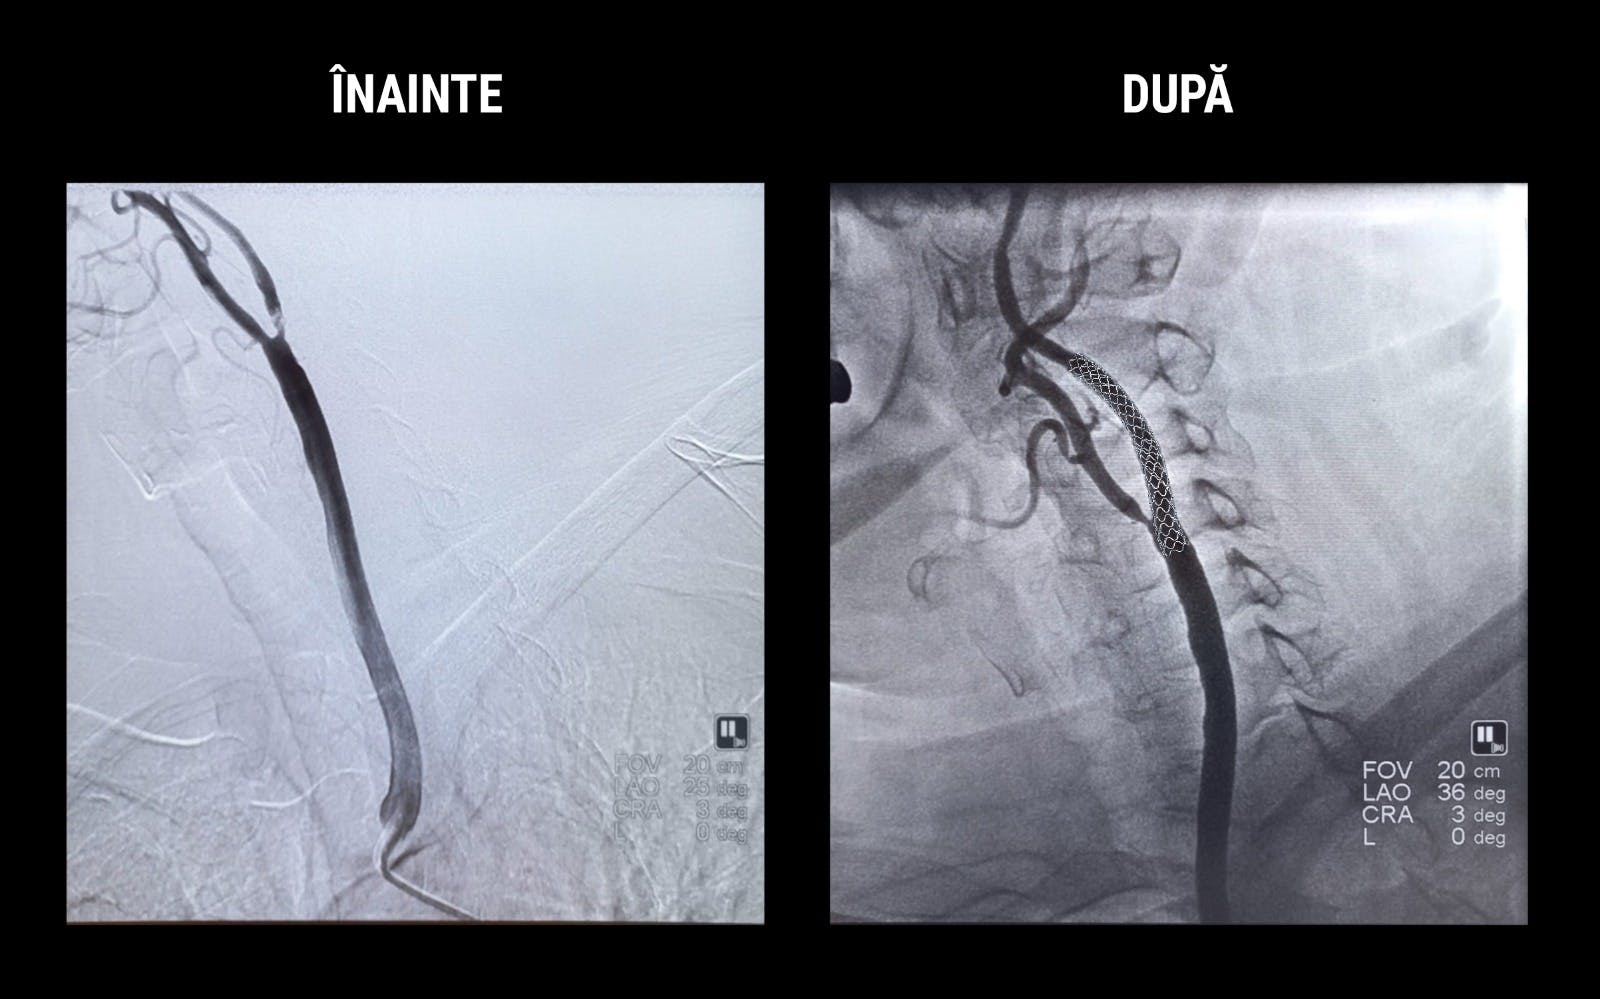

Rezultatul Angio CT-ului carotidian a arătat o subocluzie de ACI stângă (artera carotidă internă stângă), iar mici zone de AVC ischemic au fost evidențiate de examenul RMN cerebral.

În urma acestor rezultate, echipa medicală a dat recomandarea de revascularizare prin implantarea unui stent carotidian.

Astfel, doctorul Nicolae Cârstea, medic cardiolog intervenționist la ARES și Dr. Cezar Uzea, medic rezident, au efectuat procedura de angioplastie carotidiană menită să redea circulația normală a sângelui la nivelul arterei. Pentru a preveni o eventuală ruptură a depozitului de colesterol de pe arteră și a migrării acestuia către creier, medicii au implantat un filtru de protecție antiembolie. Secundar acestei manevre, dar foarte important, este implantat stentul. Acesta are rolul să mențină artera deschisă și să reducă riscul de restenozare.

Procedura a fost efectuată cu succes, starea pacientei este stabilă și urmează să continue monitorizarea neurologică periodică.